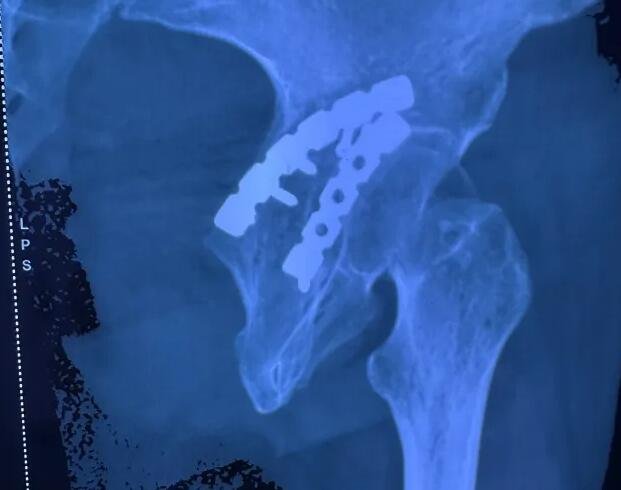

半年前,厉女士不幸遭遇车祸,导致髋关节损伤,髋臼骨折,在当地医院接受手术救治之后,出现了一个麻烦的问题:大腿后侧向下直达足趾处持续不断地麻木、疼痛,白天有其他事情分散注意力,尚可忍耐;而一到要睡觉的时候,疼痛愈发难忍,夜夜无法入眠。当地医院医生检查后,怀疑厉女士坐骨神经受损,但当地并没有对应的治疗手段。

△患者因髋部受伤,曾接受钢板固定治疗。